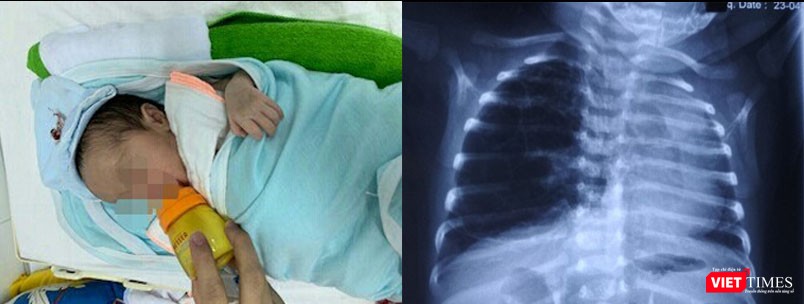

Ngày 13/5, TS. Nguyễn Việt Hoa - Trưởng khoa Phẫu thuật nhi và trẻ sơ sinh, Bệnh viện Hữu nghị Việt Đức, cho biết các bác sĩ đã cứu chữa thành công một em bé sơ sinh là Nguyễn D.A bị dị dạng đường dẫn khí phổi bẩm sinh. Nhờ đó, bé đã không còn biểu hiện của bệnh tật và bú mẹ bình thường.

Bé D.A bị dị dạng đường dẫn khí phổi bẩm sinh.

Theo TS. Nguyễn Việt Hoa, dị dạng đường dẫn khí phổi bẩm sinh là một trong những dị tật hiếm gặp ở trẻ, nhưng rất nặng nề. Dị dạng khiến trẻ bị khó thở, suy hô hấp, tràn khí màng phổi. Một phần của phổi thai nhi phát triển bất thường, có nhiều nang to, nhỏ khác nhau như chùm nho, nhưng không có chức năng hô hấp như phổi bình thường, dễ bị nhiễm trùng nhiều lần.

Biểu hiện bệnh khá đa dạng, các dấu hiệu có thể phát hiện ngay từ khi trẻ còn trong giai đoạn sơ sinh như khò khè, thở co kéo, tím tái, viêm phổi tái đi tái lại nhiều lần, suy hô hấp cấp, nhiễm trùng cấp hoặc có biểu hiện giống với các bệnh lý hô hấp khác khi trẻ lớn hơn.

Khi mắc dị tật bẩm sinh này, trẻ phải phẫu thuật cắt bỏ nang dị tật. Tuy nhiên đây là ca phẫu thuật khó do trẻ còn nhỏ, phẫu trường hẹp, đòi hỏi phải có điều kiện về gây mê hồi sức, phẫu thuật viên có trình độ, khéo léo.